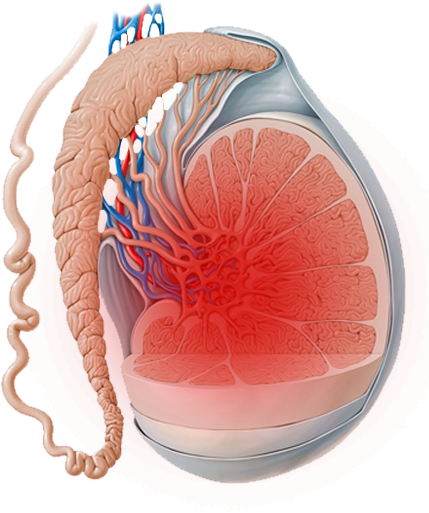

Tengo como compromiso mejorar la salud de nuestra comunidad y promover la prevención de patologías que afectan al aparato urinario, glándulas suprarrenales y retroperitoneo de ambos sexos, y el aparato reproductor masculino.

El Dr. Alejandro Palmeros Rodríguez es un médico especialista en urología comprometido con el bienestar de sus pacientes. Mediante su conocimiento y el uso de tecnología puede lograr la recuperación de distintos padecimientos y lograr una vida sana.